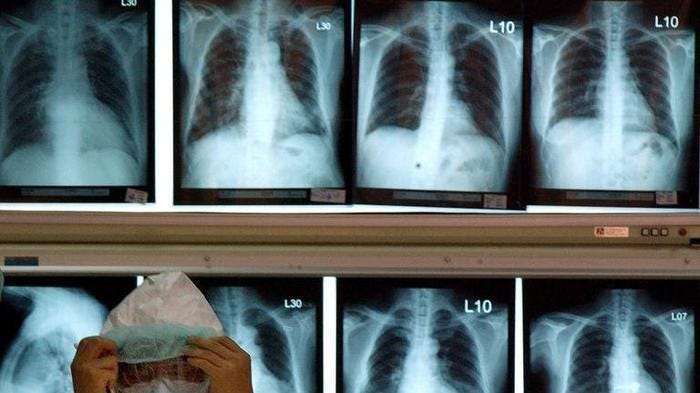

COVID-19 is more contagious but less deadly than SARS. The mortality rate of COVID-19 is between 1-2% versus 9.6% for SARS. Meanwhile, COVID-19 has spread much faster and infected over 75,000 people in 2 months compared to SARS, which took 8 months to affect over 8,000. Nonetheless, the two coronaviruses share many similarities as they have the same binding site and exhibit similar lung x-rays. However, it appears that COVID-19’s protein has larger spikes that make it more easily bind to receptors in humans, making it more contagious than SARS. Read the full article here.